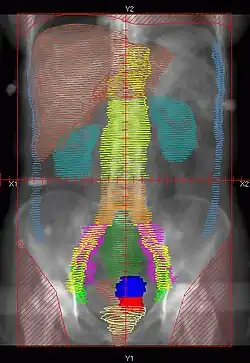

RT Technique

- There are multiple techniques, but typically Whole Abdomen RT is given to 22.5-25 Gy, followed by boost to PA LNs and whole pelvis to 45-50.4 Gy

- Dose: 22.5-25Gy in 130-150cGy/fx.

- Simulation: Supine with Alpha cradle.

- Fields: AP/PA single fields or 4-field technique

- Blocks:

- Kidneys – 50% transmission block or block after 15Gy.

- Liver – Block at 25Gy. Block not used by some institutions.

![]() |

Example of a AP whole abdomen/pelvis radiation therapy treatment field used at Tufts/Brown residency program. Actual patient contours should guide field design.